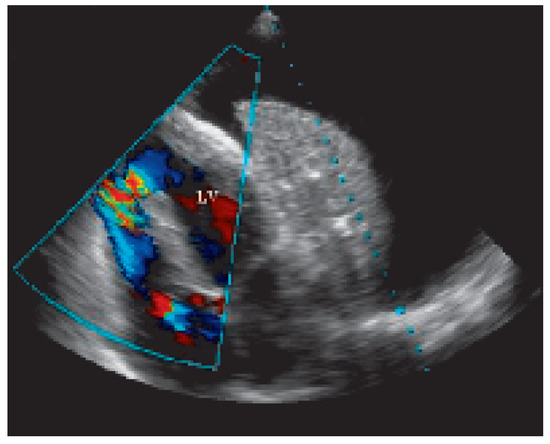

Traumatic Tamponade and Ventricular Septal Defect

A 30-year-old man sustained a knife wound in the 9th left intercostal space when he was involved in a fight as a bodyguard in a night club [...] Full article

Show Figures

Figure 1